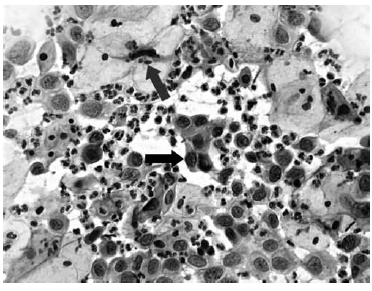

Nas questões de números 46 a 60, assinale a alternativa que melhor corresponde ao diagnóstico do quadro microscópico apresentado.

Atipias de células glandulares.